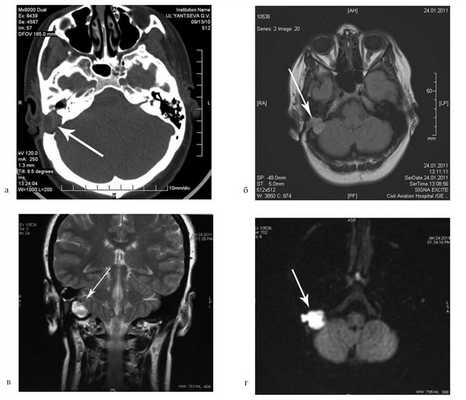

Больная Ф., 30 лет, обратилась с жалобами на головокружение, снижение слуха на правое ухо, слизистое отделяемое из правого уха. Болеет в течение 6 лет, лечилась консервативно. При отомикроскопии визуализируется перфорация в верхнем отделе барабанной перепонки.

![]()

Пациентке была выполнена МРТ основания черепа по описанной методике (рис. 1). Рисунок 1. МРТ основания черепа больной Ф. с хроническим правосторонним гнойным средним отитом. Фистула лабиринта. Холестеатома. а — исследование в режиме Т1; б — в режиме Т2; в — в режиме non-EPI DWI.

В режиме Т1 справа определяется образование с низкой интенсивностью сигнала, а в режиме Т2 и non-EPI DWI — образование с гиперинтенсивным сигналом. Диагноз: хронический правосторонний гнойный средний отит; холестеатома; фистула лабиринта. Пациентка была подвергнута санирующей операции на правом ухе с тимпанопластикой и облитерацией паратимпанальных пространств. Были выявлены холестеатома, заполняющая аттик, адитус, антрум, деструкция цепи слуховых косточек, фистула латерального полукружного канала. Послеоперационный период протекал без особенностей, на 15-е сутки была удалена гемостатическая губка и силиконовая выстилка. При контрольном осмотре ухо сухое, отмечает улучшение слуха, головокружения нет. Через 12 мес проведено повторное МРТ-исследование. Признаков холестеатомы не обнаружено. Получен хороший функциональный результат — ухо толерантно к воде, самоочищается.